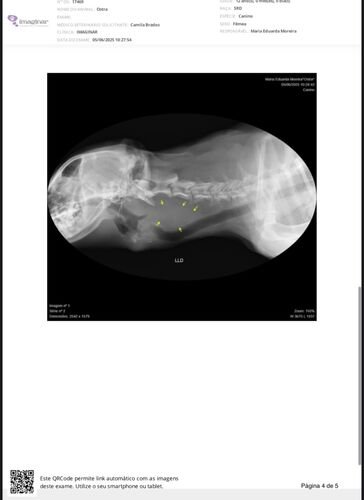

Após algumas consultas veterinárias, fomos informados da possibilidade de a Ostra estar com uma neoplasia tireoidiana, cuja natureza (benigna ou maligna) ainda não foi possível identificar. Para investigar essa condição, entre os meses de junho e julho, já realizamos diversos exames, como ultrassonografia, hemogramas, citopatologia, entre outros, com o objetivo de preparar a realização do exame histopatológico (remoção cirúrgica da massa no pescoço e biópsia).

No entanto, o médico veterinário que acompanha o caso informou que ainda são necessários dois exames fundamentais antes da cirurgia: tomografia computadorizada e ecocardiograma. Esses exames irão verificar quais órgãos podem estar sendo comprometidos pela massa em seu pescoço e se há condições clínicas para submetê-la à anestesia geral.